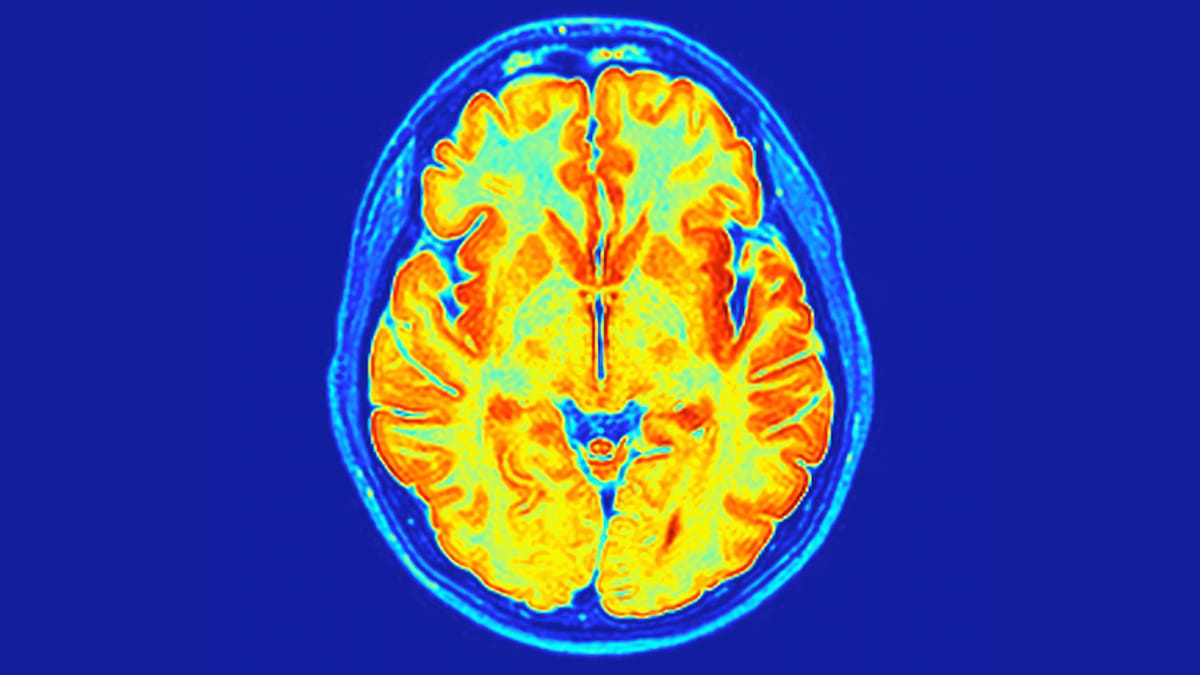

Pesquisadores identificaram um novo transtorno neurodesenvolvimental, denominado ReNU2 syndrome, que é influenciado por fatores genéticos. Essa descoberta pode proporcionar diagnósticos precisos para milhares de crianças e suas famílias em todo o mundo.

A identificação do ReNU2 syndrome oferece uma explicação molecular clara para muitas famílias que enfrentavam longos períodos de incerteza em relação ao diagnóstico de seus filhos. A pesquisa sugere que a condição pode se manifestar através de atrasos no desenvolvimento, dificuldades de fala e problemas de movimento. A compreensão do transtorno é crucial para o desenvolvimento de estratégias terapêuticas futuras.